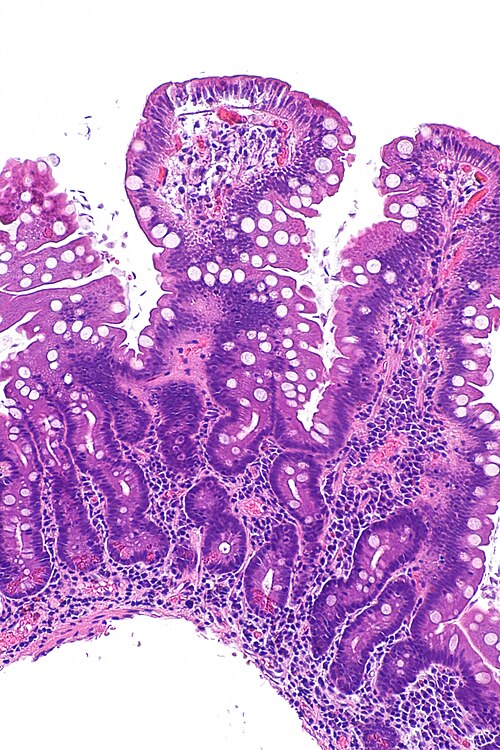

duodenum

Primary image

Very low magnification. H&E stain.